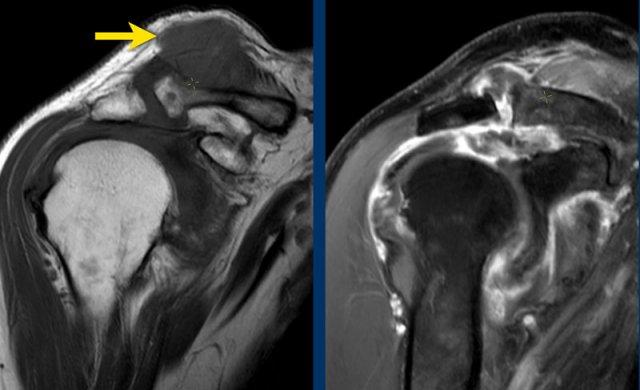

Ca lâm sàng 3

Các hình ảnh này cho thấy nang khớp cùng-đòn, còn được gọi là dấu hiệu Geyser, là biểu hiện thứ phát của bệnh lý chóp xoay.

Dịch lan lên trên vào trong và ra ngoài khớp cùng-đòn đã thoái hóa, kèm theo phá vỡ bao khớp cùng-đòn phía dưới.